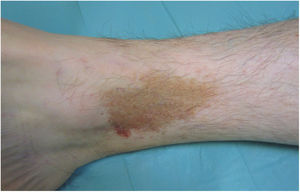

Liquen aureus o liquen purpúrico1,2,27Es una variante más localizada, generalmente única o con escaso número de lesiones, y persistente en el tiempo. Cursa con la aparición brusca de pequeñas pápulas amarillo-anaranjadas, de aspecto liquenoide con tendencia a confluir en placas de entre 1 y 20 centímetros, asociadas a lesiones purpúricas milimétricas (fig. 3). La localización más frecuente son las extremidades inferiores, aunque pueden aparecer en cualquier zona. Suelen ser asintomáticas. En niños y adolescentes se han descrito variantes zosteriformes28 y segmentarias siguiendo líneas de Blaschko29, o la distribución de las venas safena30 y cefálica31.